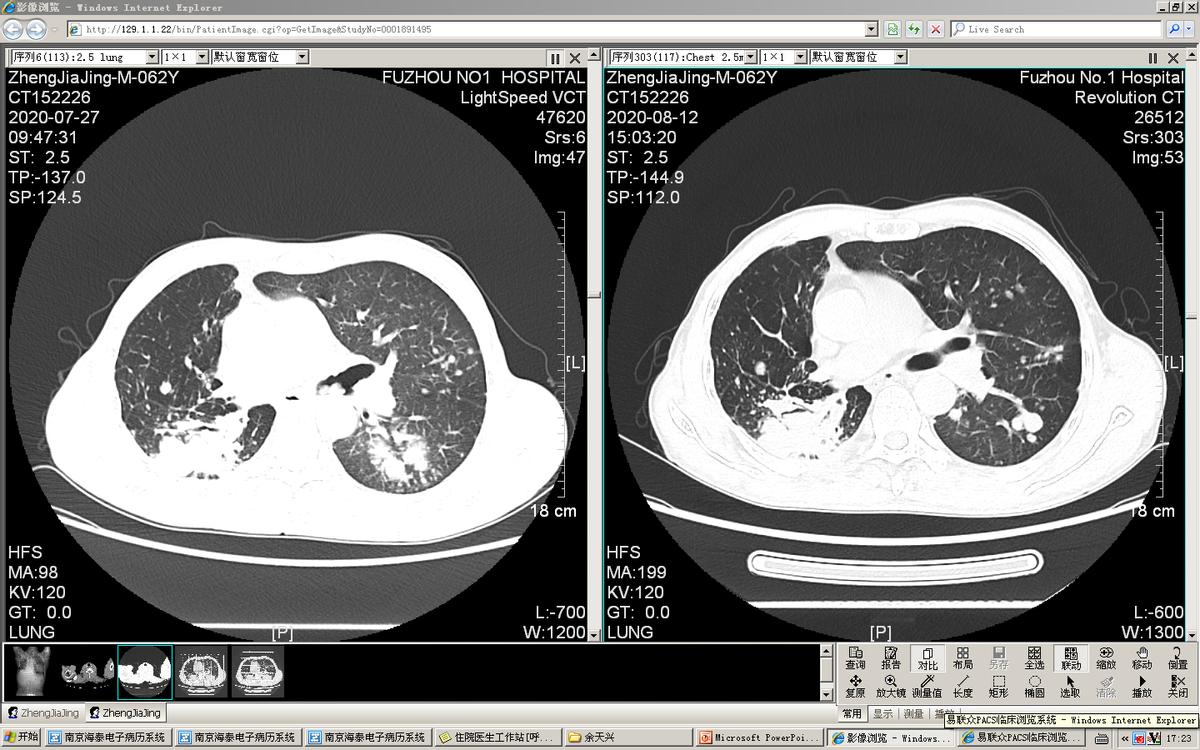

最严重的一次是1年前李先生喘得都动不了,家里人叫了救护车送过来治疗。查肺CT可见肺部里面及气道里面多处肿瘤复发、转移。

这次因为李先生状态不好,而且气管内肿瘤多,气道堵塞严重,手术风险高,我们团队讨论后,觉得用硬质气管镜联合电子支气管下对李先生气道内肿瘤进行切除比较安全。很庆幸,虽然手术比较难,但是手术很顺利,我们把气管内的肿物都清除干净了。切完后李先生气喘也明显好转了,最后他是自己走着出院的。